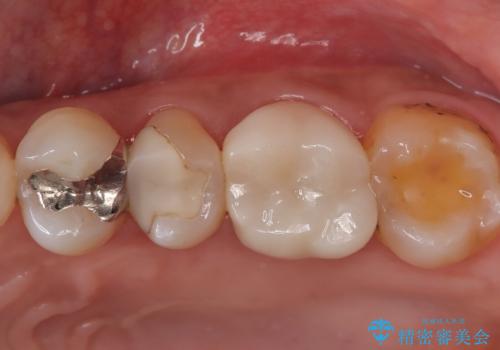

検査で見つかった虫歯 セラミッククラウンでの治療

担当医 岡田康成